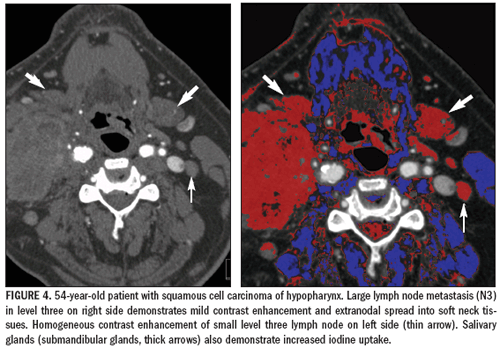

Iodine maps acquired in this manner can be used to highlight contrast enhancement in tissue (for instance, in lymph node metastasis) and to help differentiate viable tumor from necrosis and surrounding tissue.

Dual-energy iodine maps cannot quantify dynamic parameters such as blood volume, blood flow, time-topeak enhancement, or mean transit time, as CT perfusion imaging can. The technique can, however, help to discern lesions with contrast uptake from those without and help monitor the effects of chemotherapy (Figures 2 to 5).